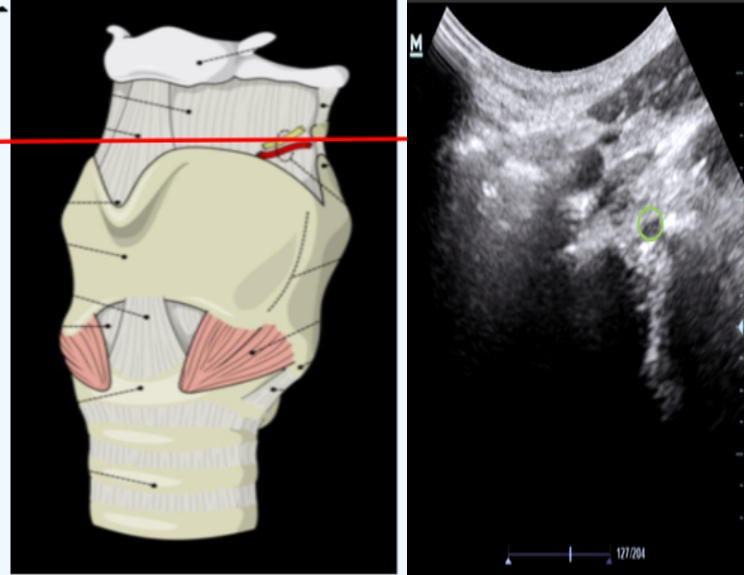

图12为甲状舌骨膜平面横向切面,红线为会厌,PES为会厌前间隙,AM为气体黏膜交界面,黄色为甲状舌骨膜平面会厌到皮肤的距离/颈前软组织距离。

图片

图12  甲状舌骨膜平面横向切面

图13为舌骨平面矢状位扫查面,红色为皮肤到舌背面的距离。黄色为扫查到的舌骨产生的伪影。

图13  舌骨平面矢状位扫查面

图14为舌骨平面横向扫查图,图中可见舌骨呈现。

图14  舌骨平面横向扫查图